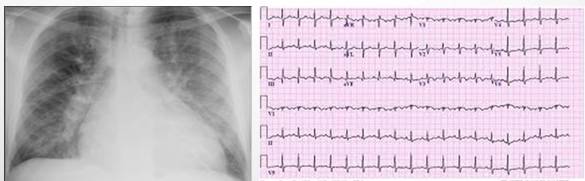

♦71岁老年男性,因严重的气促、双下肢水肿就诊;

♦既往因慢性心力衰竭病史反复住院治疗;

♦Na+ 130mmol/L Scr 146μmol/L HGB 92g/L ALB 28g/L;

♦在急诊科予以120mg速尿后转至CCU予以硝酸甘油静脉泵入;

——开始排出500ml小便

——次日清晨复查 Scr 320μmol/L

——再次予以速尿后患者无小便

——血压维持不住……